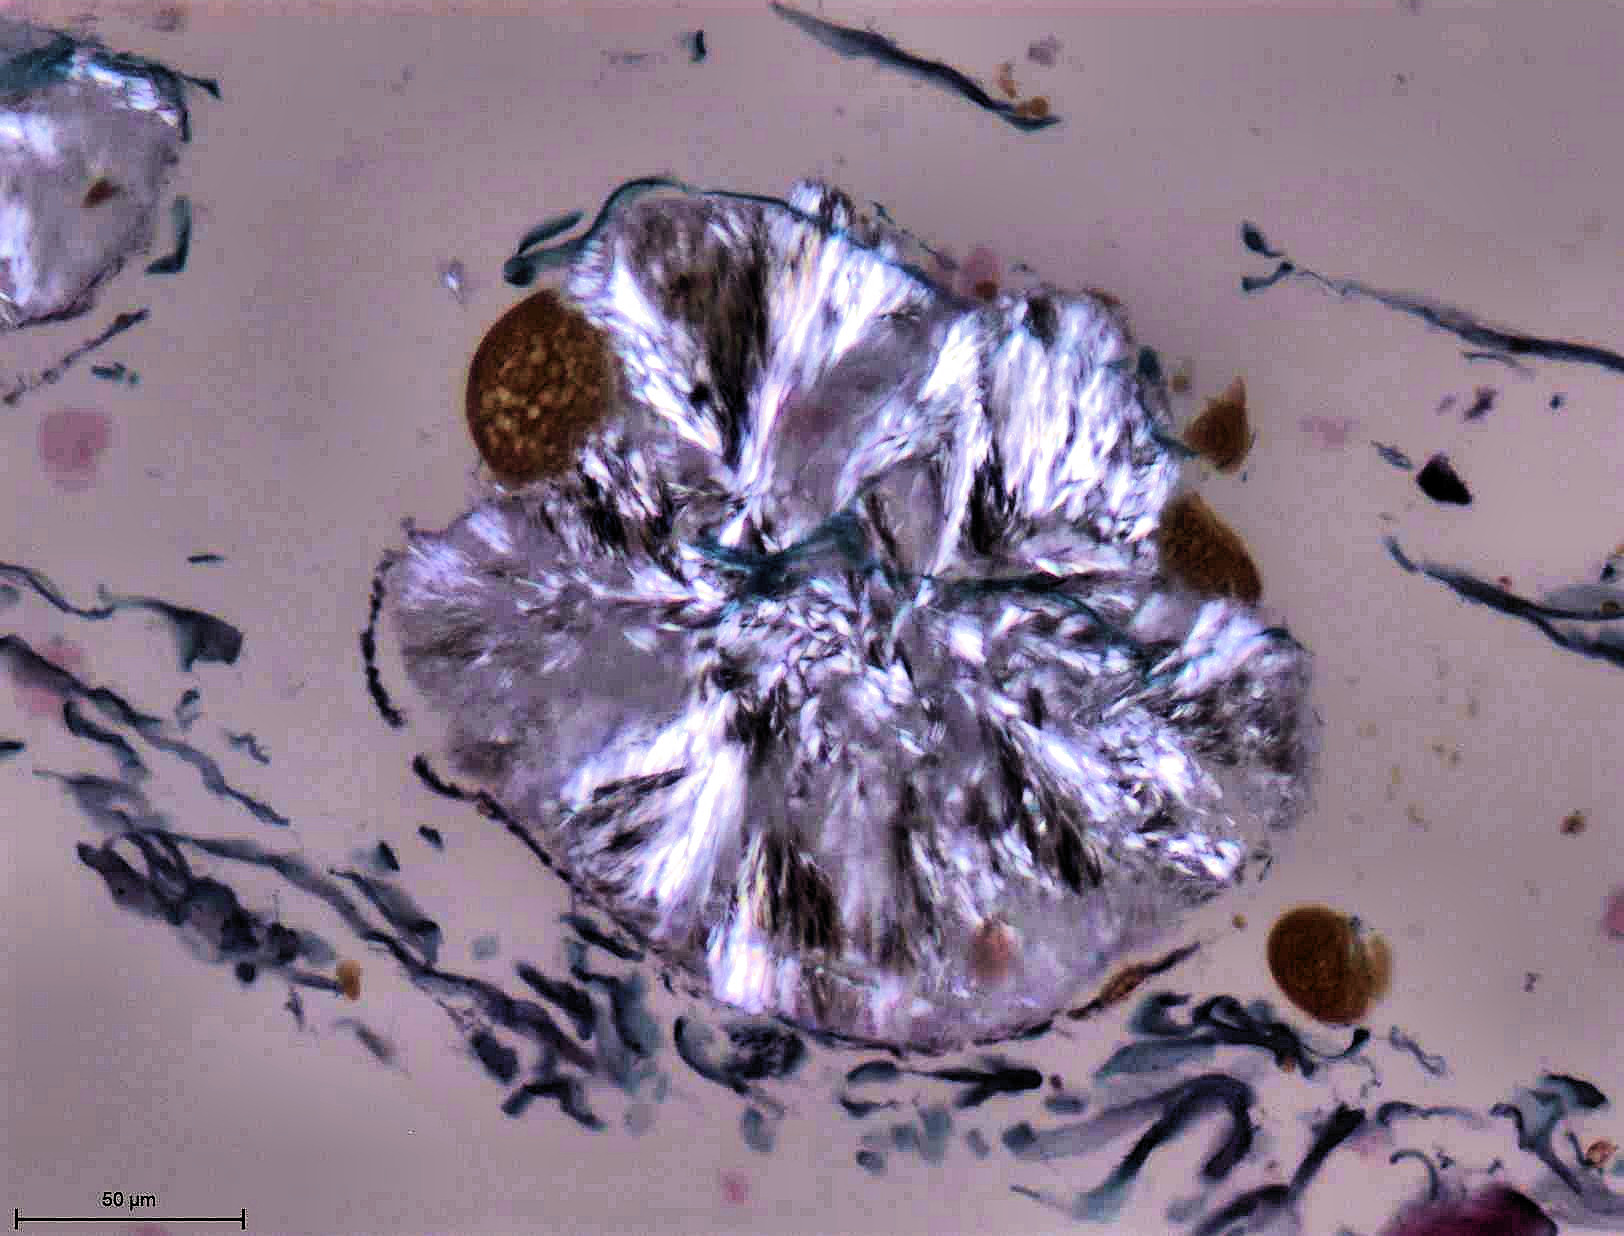

Le laboratoire d’histologie est essentiellement dédié à l’examen du squelette et des tissus mous putréfies ou momifiés dans un contexte d’anthropologie médicolégale. L'examen microscopique des tissus permet :

• de confirmer la nature humaine ou non des fragments osseux

• d’estimer le délai post mortem et donc l’origine ancienne ou récente des ossements

• de mettre en évidence la nature pathologique ou traumatique d'une lésion osseuse et d’en évaluer le délai post traumatique

• de déterminer la nature de particules exogènes animales, végétales ou autre dans des tissus putréfiés ou momifiés